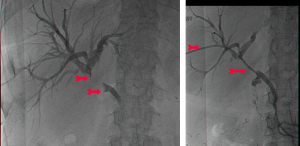

שיטה נוספת לניקוז דרכי המרה תוארה בראשונה ב-1980. בשיטה זו דרכי המרה החסומות מנוקזות בעזרת תותב שהוחדר ישירות דרך פטמת Vater לתוך צינור המרה המשותף. החדרת התותב בוצעה בעזרת אנדוסקופ במהלך ERCP (תצלום 53.8). הפעולה מצליחה ב-90% מהמקרים, ושכיחות התחלואה היא 10%. התמותה המדווחת בעקבות פעולה זו היא בשיעור 2%, והתמותה הסב-פעולתית (בתוך 30 יום) היא בשיעור של כ-10%. הסיבוך השכיח ביותר הוא דלקת עולה בדרכי המרה (8%). סיבוך שכיח נוסף הוא חסימת התותב וצהבת חסימתית גוברת.

פעולות להקלה יכולות להתבצע גם דרך ה-PTC. לאחר הדגמת דרכי המרה מחדירים צינורית קשיחה שבה נקבים רבים, ובשיטה מיוחדת, בהנחיית שיקוף, חודרים את השאת החוסמת ומעבירים חלק מהצינור מעבר לחסימה, כך שהמרה יכולה לזרום דרך נקבים אלה לתוך התריסריון. שיטה זו חוסכת ניתוח בשלביה המתקדמים של המחלה.